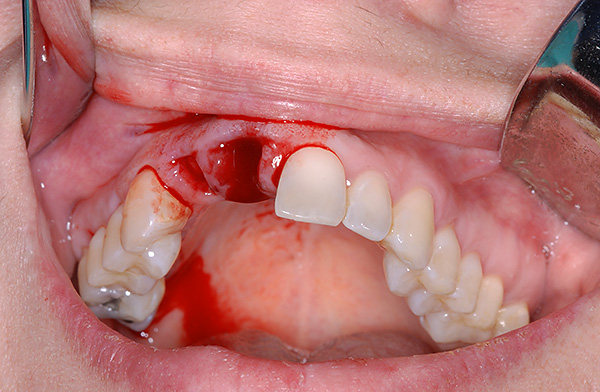

O implante dentário imediato (isto é, imediatamente após a extração de um dente doente) está ganhando cada vez mais popularidade a cada ano. Para alguns especialistas neste campo, o número de implantes imediatos é de 40 a 50% do volume total de trabalho, e o sucesso de tais operações depende diretamente do profissionalismo do médico e da disponibilidade do equipamento necessário na clínica odontológica.

Antes de falar sobre as muitas vantagens do implante imediato, lembramos mais uma vez que esse processo é chamado não cirúrgico, como se costuma dizer, “a linguagem não muda”. E sim, pode não haver uma incisão gengival, uma vez que não é necessária, porque um novo orifício em um dente que acabou de ser removido muitas vezes já é adequado para a colocação do implante sem manipulações adicionais com um bisturi.

Quando não há contra-indicações para implante imediato, e o médico possui a experiência e o suporte técnico necessários, o procedimento oferece vantagens significativas sobre o implante clássico:

- No caso de implante simultâneo, a extração dentária, a instalação de um implante e um formador de goma são realizadas em uma visita à clínica;

- Na área de extração dentária, a deficiência óssea não tem tempo para se formar devido a uma ausência prolongada de carga mastigatória. Isso significa que a instalação do implante não requer uma operação de elevação do seio (extensão óssea);

- É mais fácil para o médico ajustar o implante no espaço de um novo furo, o que ajuda a calcular e controlar corretamente o processo de instalação, e isso, por sua vez, tem um efeito positivo no resultado final e na facilidade de uso de futuras estruturas ortopédicas (pontes, coroas, etc.).